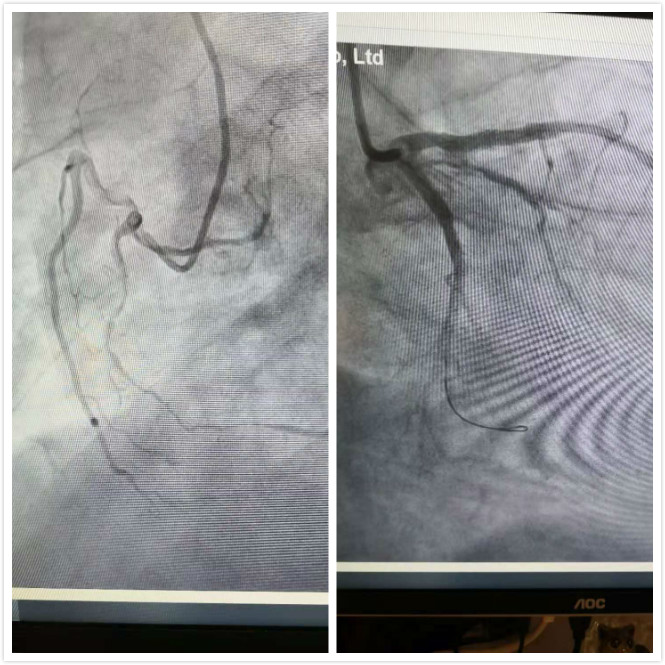

我院心内科介入团队结合患者实际情况,认为对其最好的诊疗方式是通过CAG(冠状动脉造影术)明确患者冠脉情况,且必要时可立即为患者进行急诊PCI(冠状动脉介入)手术。方案确定后,医护人员抓紧急诊PCI时间窗,迅速做好PCI术前准备并开通绿色通道。通过右桡动脉穿刺手术显示患者前降支闭塞、旋支、右冠严重狭窄,三支病变,急性ST段抬高型前壁心肌梗死。介入团队立即为患者开通前降支行介入治疗。由于患者ST段抬高型心肌梗死,导致患者术中症状反复发作,血压处于下降状态,难以稳定。术中医护人员共同协作,取药配药、静脉注射、稳定血压等操作忙而不乱。终于历经70分钟顺利为患者完成了急诊PCI手术,患者胸痛症状消失,转危为安。